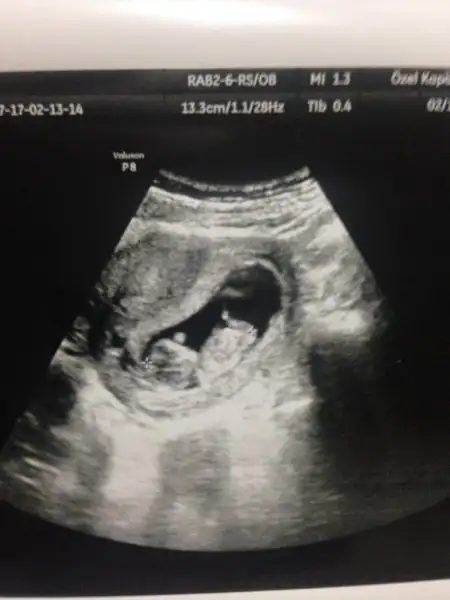

Normalde 8 haftalik ama 7+1 çıktı kalp atisini duyduk çok şükür sol tarafta benimki seninki?

kız gibi canım. Şöyle usg resmini eline aldığında eğer karından usg ise bebek kesenin sağına yakınsa kız soluna yakınsa erkek, vajinal usg ise tam tersi. Buarada sesin ultrason resmi benimkine çok benziyo bebeğin kesedeki konumu olarak

Kizlar bugun tekrar gittim doktora,8 haftalikken bebek kesenin sagindaydi.simdi 10 haftalik,cok kipirdak sanirim sola yaklasmis.bu kese ve cinsiyet konusu kac haftalikken dogru oluyor? Bidaha bakarmisniz bana